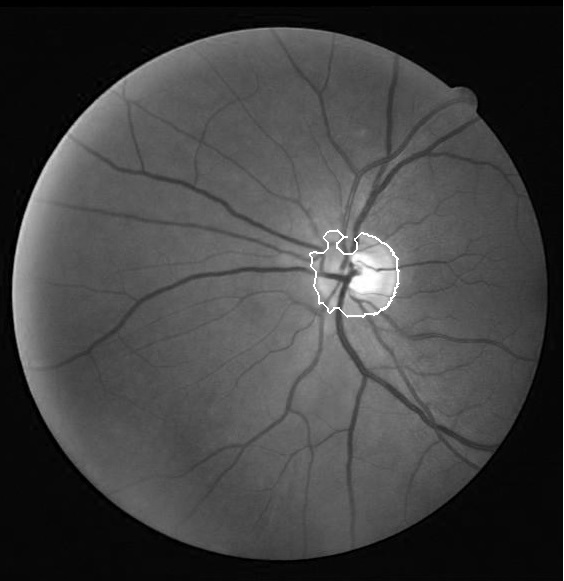

We applied our algorithm on 40 images of DRIVE dataset111http://www.isi.uu.nl/Research/Databases/DRIVE/and 50 images of Khatam database222Images of this database are gathered by Khatam-Al-Anbia eye hospital, Mashhad, Iran. In both datasets the optic disk boundary is hand labeled by an ophthalmologist as ground truth. Fig. 3 and Fig. 4 show our results on the DRIVE and Khatam databases respectively. The results show that our algorithm is robust to changing illumination and also to abnormal retinal images. The result on the second image of Khatam dataset (Fig. 3) shows that our algorithm can distinguish between parapapillary atrophy boundary and optic disk boundary.

In the first step, we need to define a window with the center of the optic disk. To accomplish this task, the center of the obtained region from the optic disk localization step is modified. The obtained region from the optic disk localization step is located at the temporal part of the optic disk. The reason is that this part is brighter than the other parts of the optic disk (superior, inferior and nasal parts. Fig 2), so the center of this area can approximate the center of optic disk height. But, this point can be the center of optic disk width if only the brightest part of the temporal side is close to the optic disk vessels. Therefore, by the information obtained from the vessel segmentation step, we adjust this point so that it gets close to the vessel. This point is used as the first estimation of optic disk center.